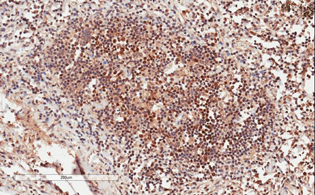

Immunohistochemistry (Formalin/PFA-fixed paraffin-embedded sections) - Biotin Anti-GRB2 antibody [Y237] (AB201539)

IHC image of GRB2 staining in a section of formalin-fixed paraffin-embedded normal human colon*. The section was pre-treated using pressure cooker heat mediated antigen retrieval with sodium citrate buffer (pH6) for 30mins, and incubated overnight at +4°C with ab201539 at 1/100 dilution. DAB was used as the chromogen (ab103723), diluted 1/100 and incubated for 10min at room temperature. The section was counterstained with haematoxylin and mounted with DPX. The inset negative control image is taken from an identical assay without primary antibody.

For other IHC staining systems (automated and non-automated) customers should optimize variable parameters such as antigen retrieval conditions, primary antibody concentration and antibody incubation times.

*Tissue obtained from the Human Research Tissue Bank, supported by the NIHR Cambridge Biomedical Research Centre.